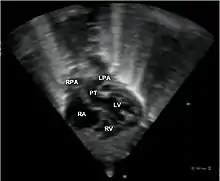

قد يكشف مقدم الرعاية الصحية عن لغط قلبي أثناء الاستماع إلى الصدر بالسماعة الطبية، ويكون لون جلد الطفل وفمه أزرقًا. وغالباً ما تشمل الاختبارات ما يلي:

- الأشعة السينية على الصدر، الأشعة السينية على الصدر، تحول الأوعية الكبرى يظهر عادة صورة ظلية للقلب المنصف على أنها "بيضة على سلسلة"، حيث القلب المتوسع يمثل بيضة على الجانب والغدة الصعترية الضامرة من المنصف العلوي تمثل السلسلة.

- مخطط صدى القلب (إذا تم ذلك قبل الولادة، يُسمى مخطط صدى القلب الجنيني)